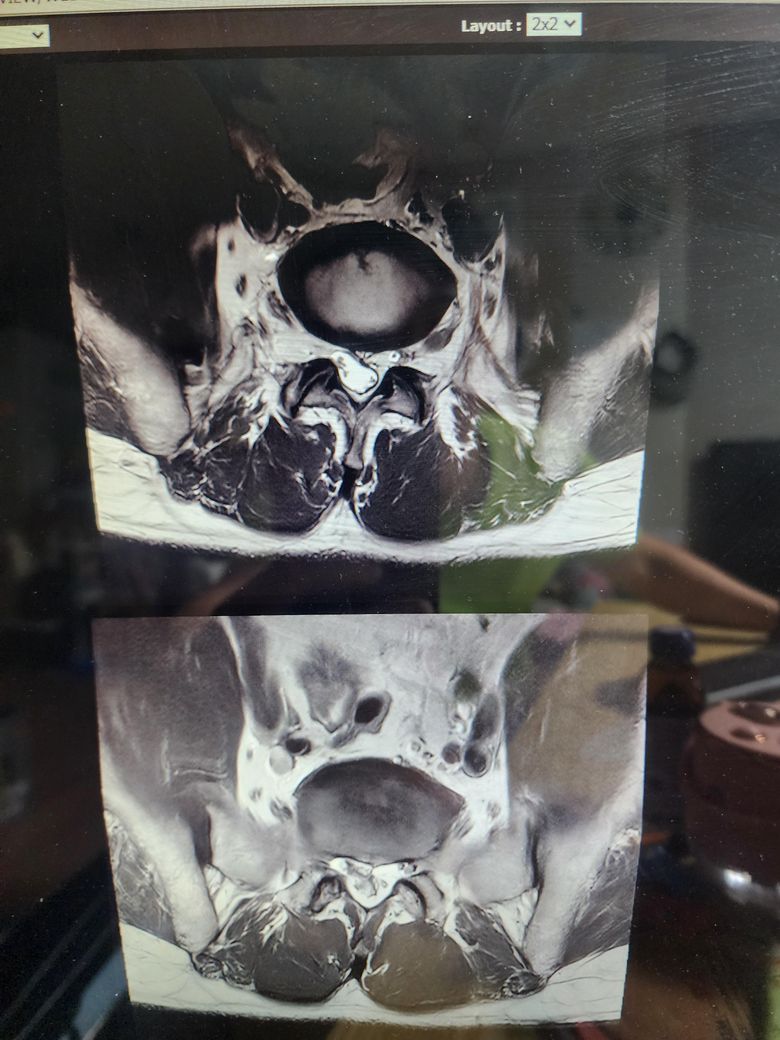

• 1번 째 사진

보여주신 MRI 상에는 척추관 협착증은 전혀 보이지 않습니다.

아래 첫번째 그림에 보시는것과 같이 B에서 보이듯이 검정색 신경뿌리 주변의 하얀색 뇌척수액이 공간 없이 비좁아지는 정도는 되어야 척추관 협착증이라고 이야기할 수 있을텐데 보여주신 MRI 에는 이런 모습은 없습니다.

정확하게는 제가 두번째로 올린 작성자분의 허리 MRI 사진중에서 빨간색 동그라미로 표시한 부분의 단면을 확인해야 더 정확한 설명이 가능하긴 하겠습니다.